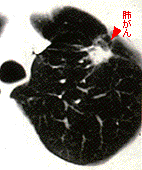

CT検査による肺がんの画像

肺がんは、がんのなかでもことにCT検査によって解析がしやすい。3〜5mm程度の小さなものまで見つけることができる。写真の白い部分ががん。